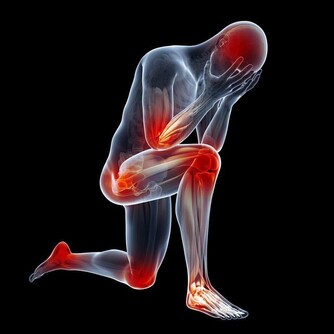

「憂鬱」器官——脾臟

脾臟功能不好的話,人會容易憂思過度,好走極端。情緒會變得不穩定,容易懷疑別人,往往會患上精神性疾病。同時,憂思也會傷脾。有趣的是,在很多古代中醫治病的故事裡,面對那些憂思過度,氣息懨懨又無葯可治的患者,聰明的大夫就會根據五行中肝木克脾土的原理,用「以情勝情」法,故意激患者發怒,讓肝氣衝破鬱結的脾氣,最後讓患者不藥而癒。這也告訴大家,過度的情緒都是會傷害我們的身體健康的,一定要注意避免。在飲食上,黃色的食物對脾有益。黃色的食品如香蕉、蘋果、紅薯、黃豆、玉米等;而甜食入脾,吃得過多會影響脾功能。